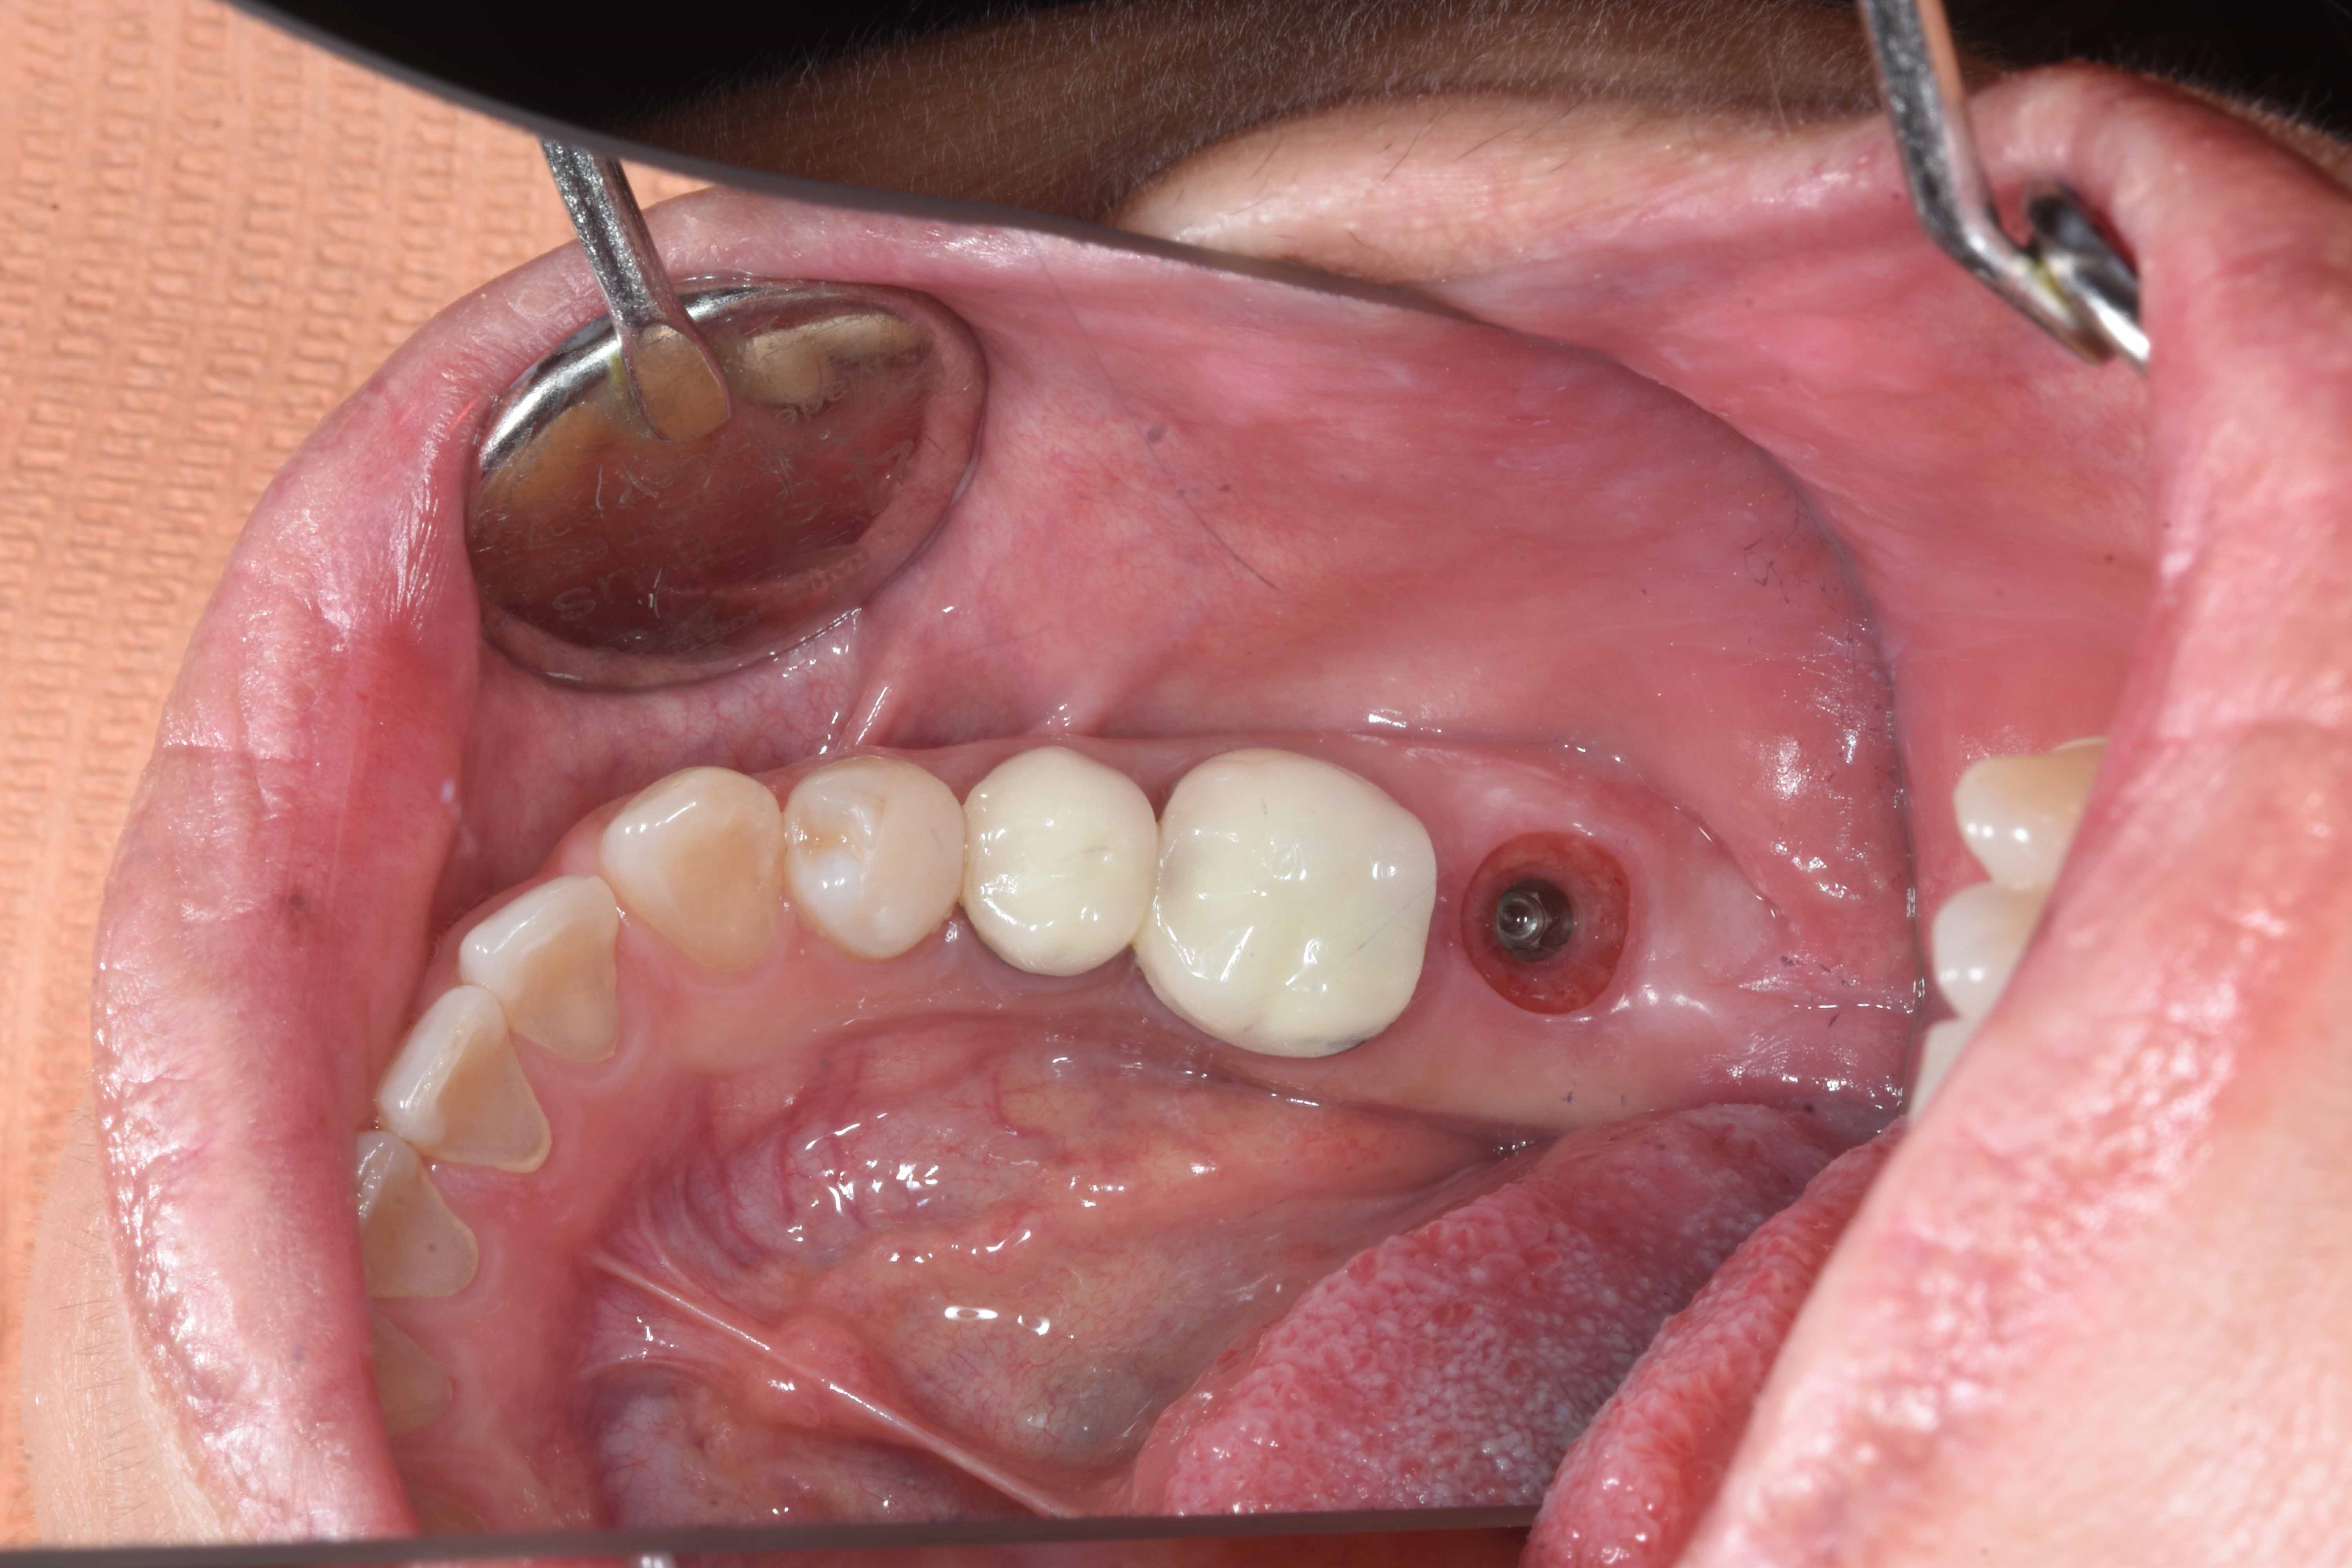

案例四

使用數年的假牙,牙根萎縮,建議拔除及植牙

醫生透過電腦斷層評估骨頭狀況決定植入的植體所放的寬度與深度

植入植體,並鎖上癒合螺帽

2-3個月癒合,7-10天完成假牙 ,試戴、調整咬合高度並鎖上,封填,完成